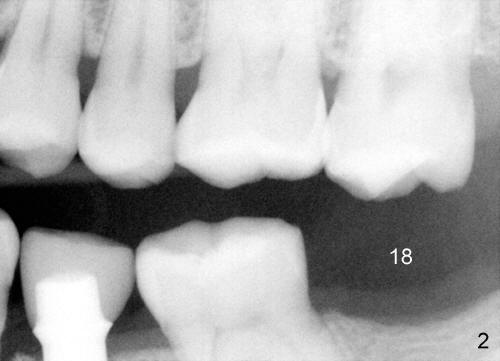

A 46-year-old man presents to clinic to fix porcelain chip over the implant crown (Fig.1 white *). The contact is loose. The patient has had history of tooth fracture, probably involving the teeth #3, 18 and 20 (Fig.2). He has habit of chewing on the right. The bone density (black *) around the implant (I) is high. All suggest bruxism.